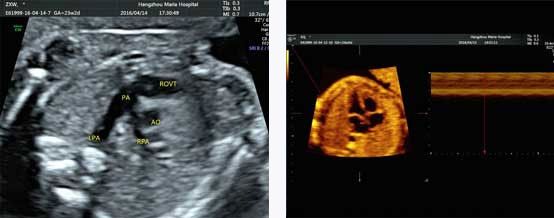

四维彩超优异的图像分辨率,能在四维空间内展现立体的心脏结构和功能,不仅能够检测高危孕妇的心脏状况,h's检查胎儿心脏发育情况。

四维彩超具备一整套成熟的胎心成像技术,支持从胎儿心脏结构到心功能的专业分析,是胎儿心脏检测评估领域的技术。双平面成像技术可实时观察胎心结构和血流变化,帮助临床医生及时作出诊断。

真实呈现胎儿胎心结构、脐带、血流变化